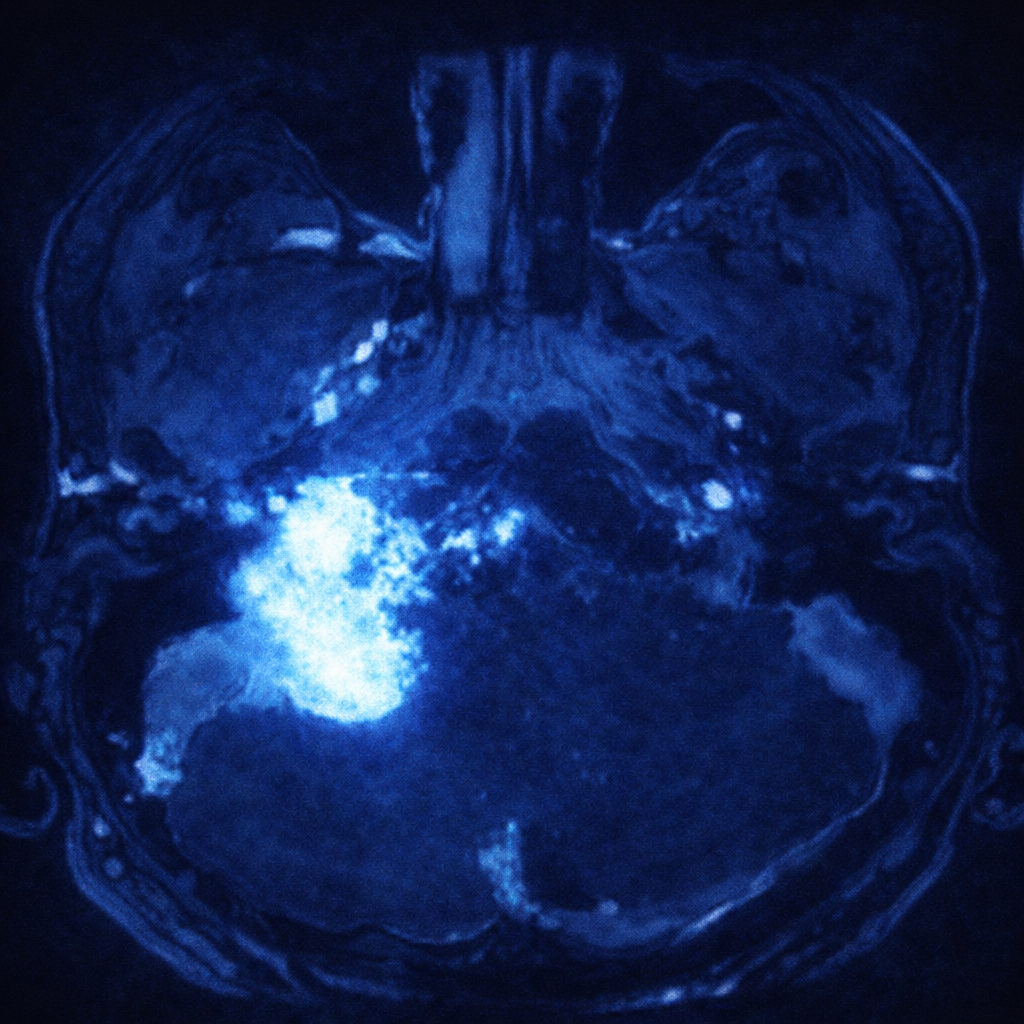

La resonancia magnética es el estudio apropiado para estudiar un glomus yugular. Generalmente, estos tumores captan medio de contraste de manera regular, aunque pueden tener grandes componentes quísticos.

En las tomografías, es característico encontrar una tumoración que amplía y erosiona el foramen yugular y el hueso temporal.

La angiografía es muy importante, ya que estos tumores son altamente vascularizados y, generalmente, se alimentan de la arteria faríngea ascendente. El estudio preoperatorio de la producción de catecolaminas también es fundamental para la prevención de complicaciones. Aunque el diagnóstico definitivo se establece únicamente al analizar un fragmento del tumor por patología.